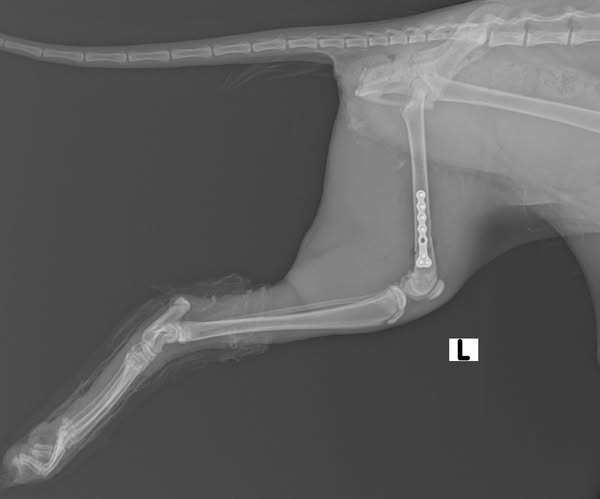

პოსტს თან ახლავს ოპერაციამდე და ოპერაციის შემდგომი რენტგენოგრაფიული გამოსახულებები, რომლებიც ხაზს უსვამს ქირურგიული ჩარევის შედეგად მიღწეულ შესანიშნავ პროგრესს. 1 თვის შემდეგ გაკეთებული რენტგენოგრაფია აჩვენებს ბარძაყის მოტეხილი ძვლის გამოსწორების და სტაბილიზაციის მნიშვნელოვან გაუმჯობესებას, რაც გუკუს შემთხვევის წარმატებულ შედეგს ადასტურებს 🩵

After careful evaluation by the veterinary team, a decision was made to proceed with surgery to address the fracture. The procedure was performed by Dr. Lasha-Giorgi Japaridze, the Clinic’s Chief Veterinarian and Head of the Surgical Department. Dr. Japaridze has extensive experience in managing complex orthopedic injuries, making him uniquely qualified for such a challenging case. The surgery involved open fracture reduction, stabilized using a titanium T-locking plate, which provides optimal support for bone healing in companion animals. Dr. Japaridze was assisted by Barbare Kurtsikidze.

Attached to this post are preoperative and postoperative radiographic images that highlight the remarkable progress achieved through surgical intervention. The 1-month postoperative images demonstrate significant improvement in the alignment and stabilization of the fractured femur, marking a successful outcome for Guku’s case 🩵